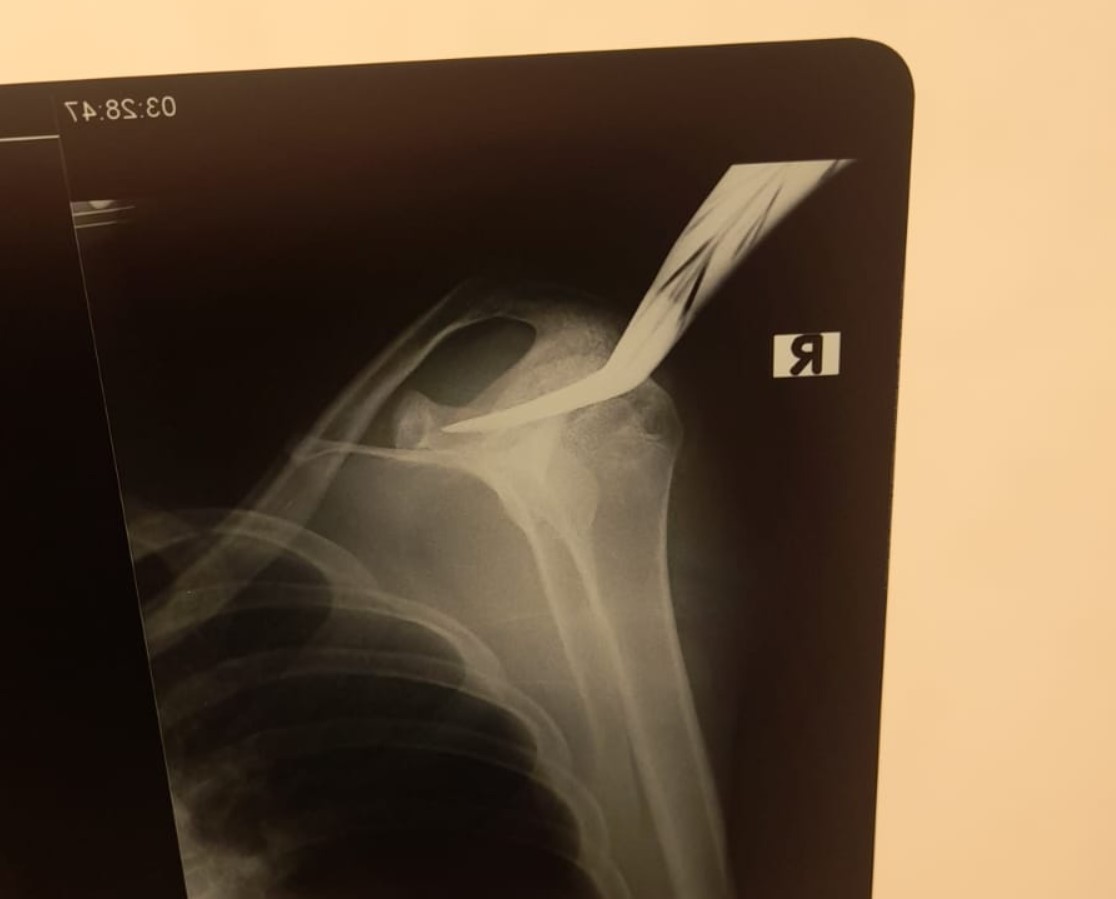

Jeffry juga menyebutkan bahwa korban kini sedang dalam penanganan medis intensif. Luka yang diderita TS akibat bacokan masuk ke tulang skapula, tepatnya di bahu sebelah kanan, dengan luka sepanjang 4 sentimeter.

“Korban dirujuk ke RS Sardjito untuk penanganan lebih lanjut,” tutup Jeffry.